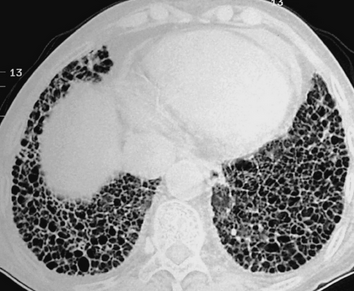

以下是圍繞肺纖維化機制與干預研究匯總的50個熱門的選題方向,涵蓋信號通路、細胞機制、中藥干預、新型療法等。

特發性肺纖維化急性加重的炎癥小體活化機制

COVID-19 后肺纖維化的病毒 - 宿主互作機制

肺纖維化動物模型與臨床病理的轉化差異研究